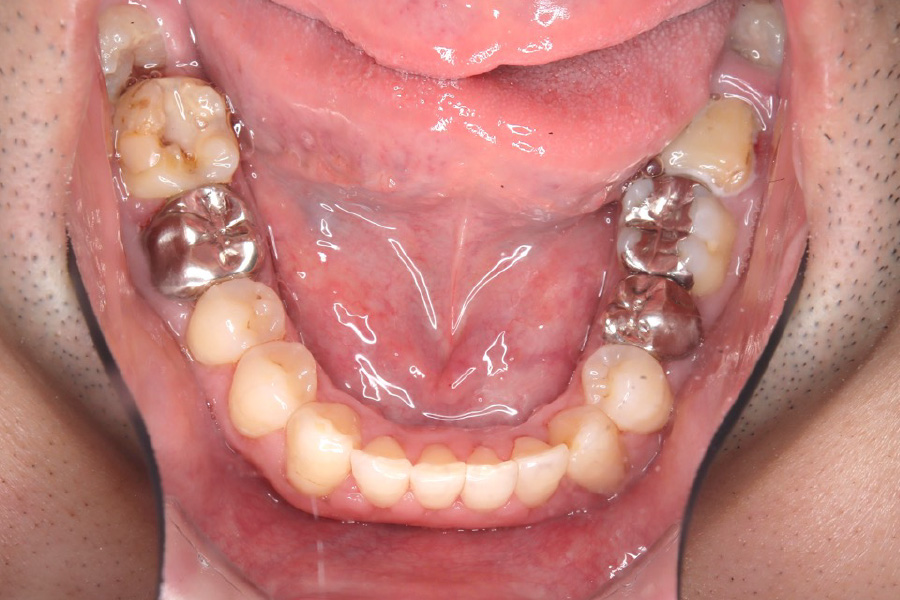

治療前

主訴 上の前歯を揃えたい

治療内容 インビザライン矯正

小臼歯抜歯